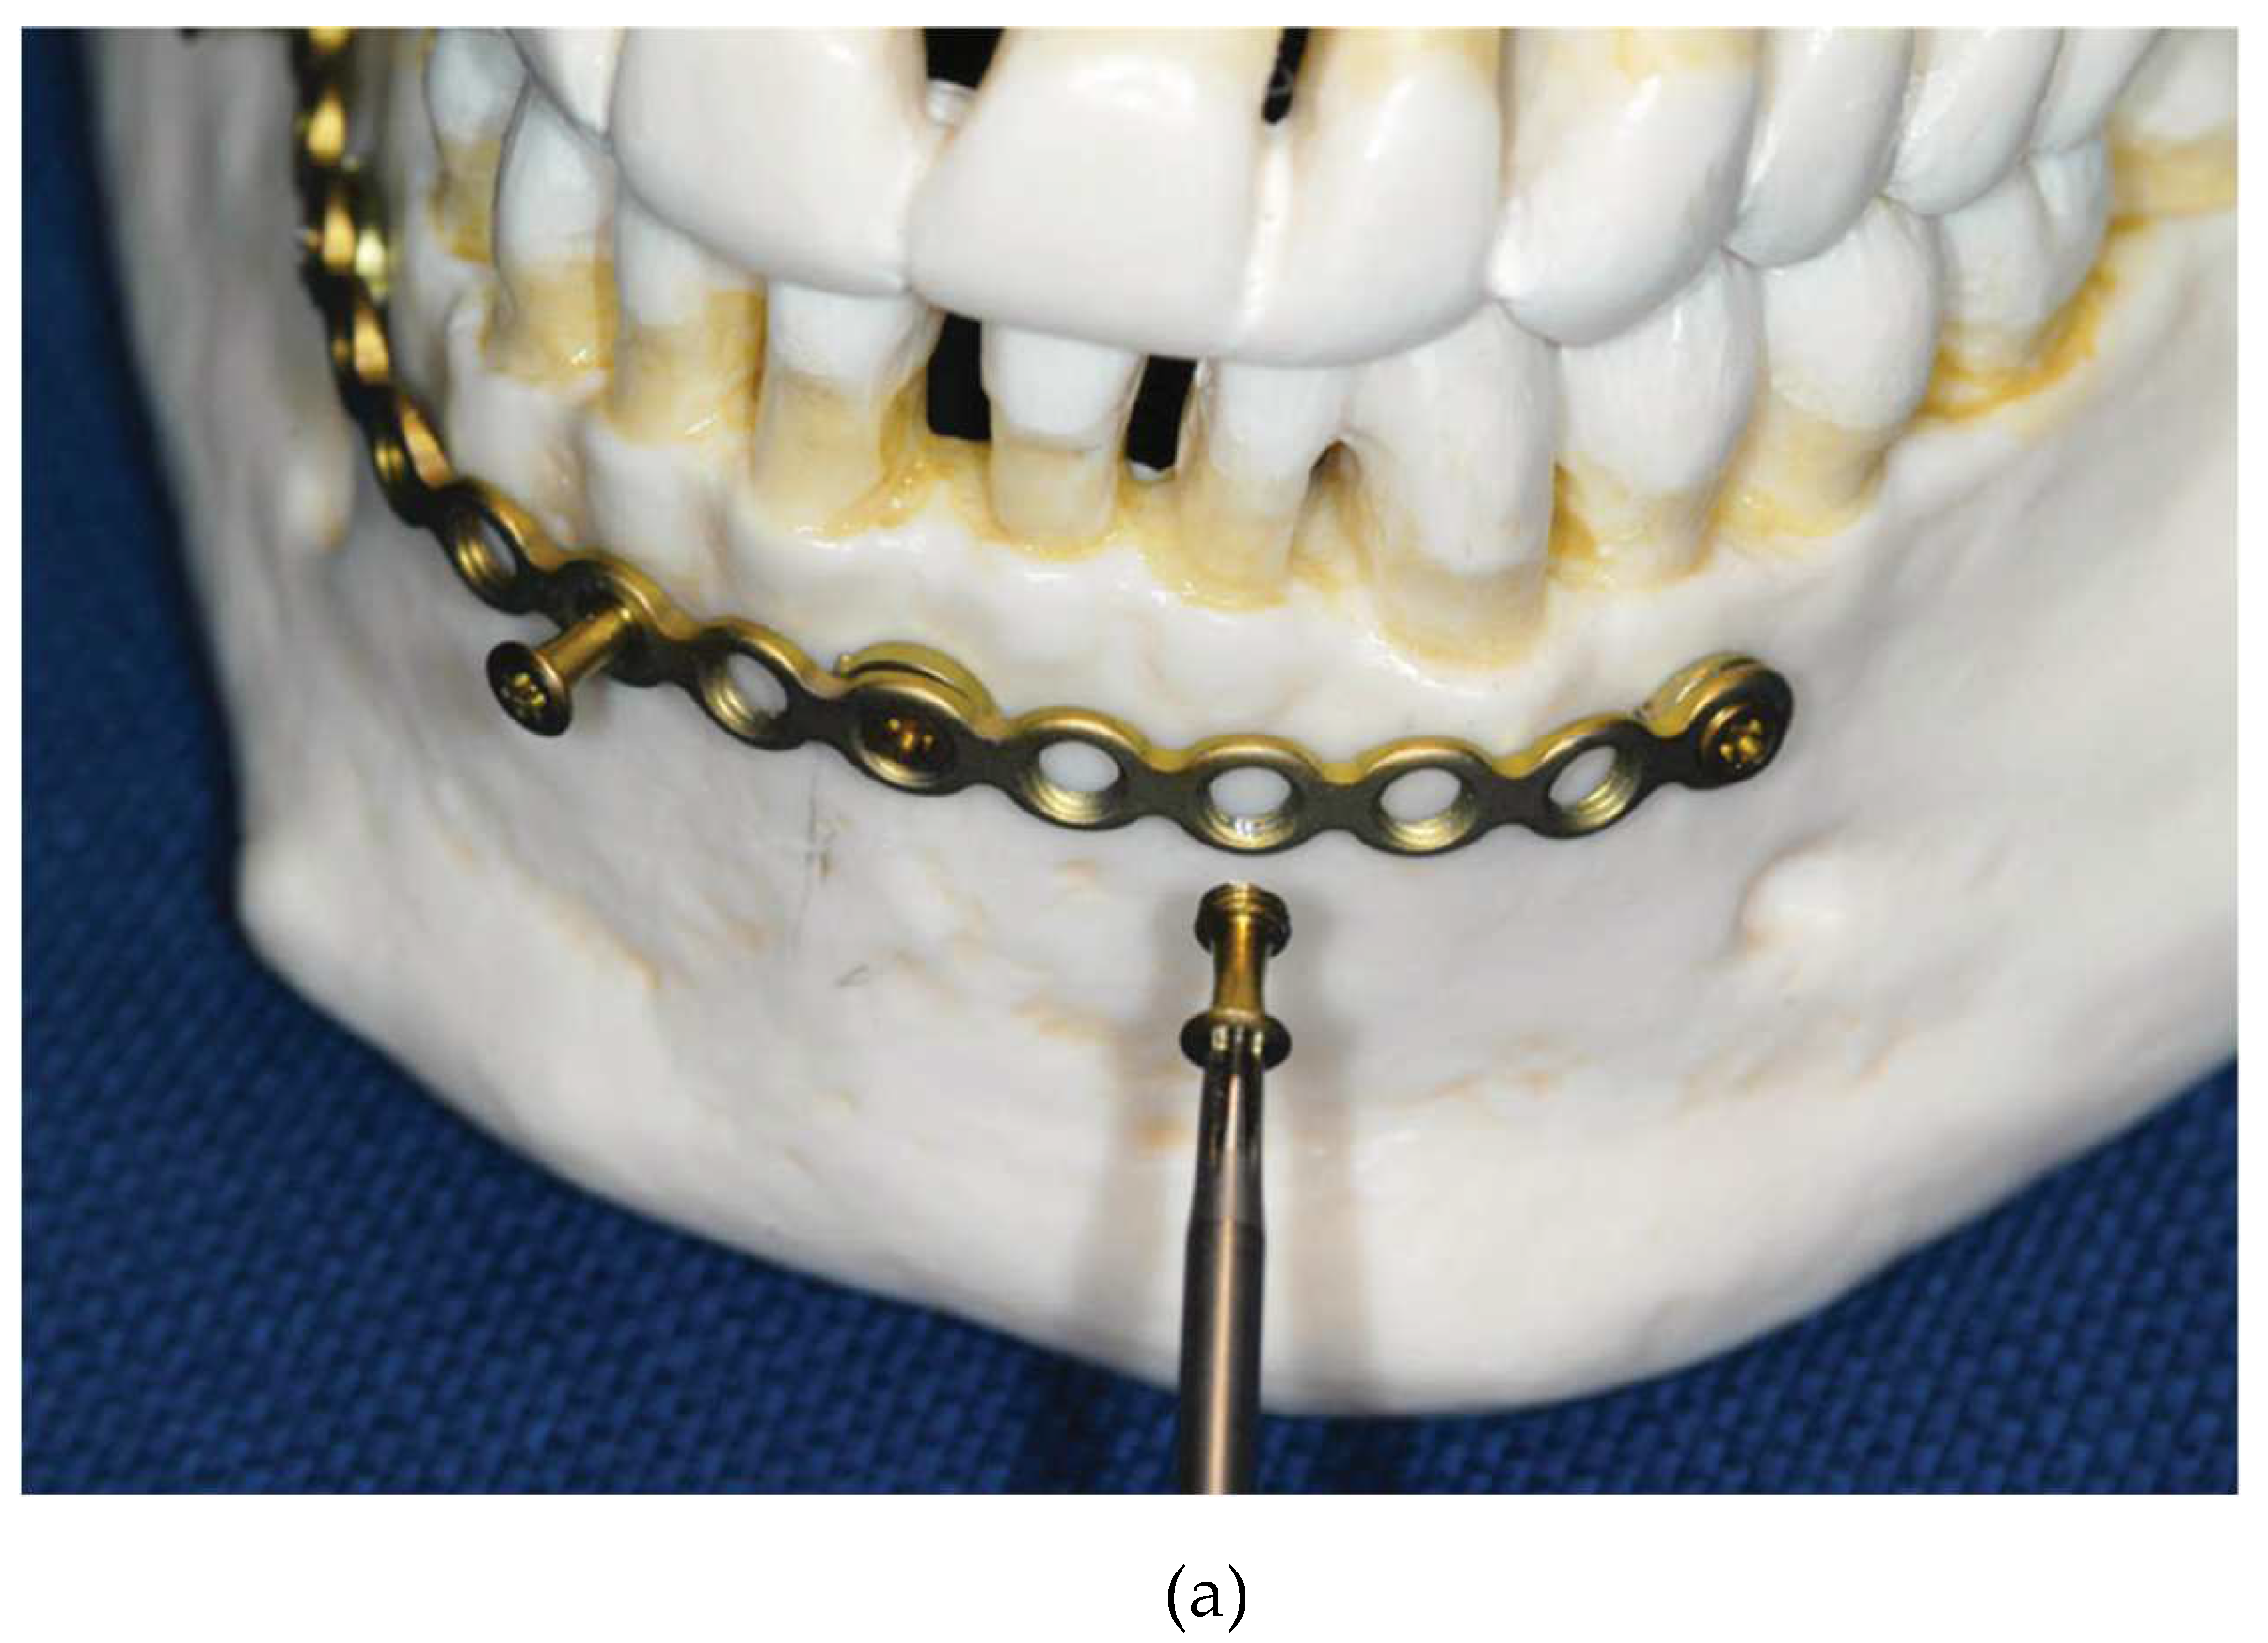

Figure 2.

(A): nsertion of an MMF nut into Locking adaptation plate. (B): Opposing locking adaptation plates in the mandible and maxillae underlaid with single hole (‘ring’) washers beneath the screw sites to keep the plate at a distance (“stand off”) to the mucosa/ bone surface and affixed MMF nuts. Source/origin of Figure 2: Plastic skull model, Photograph collection – C.P. Cornelius.